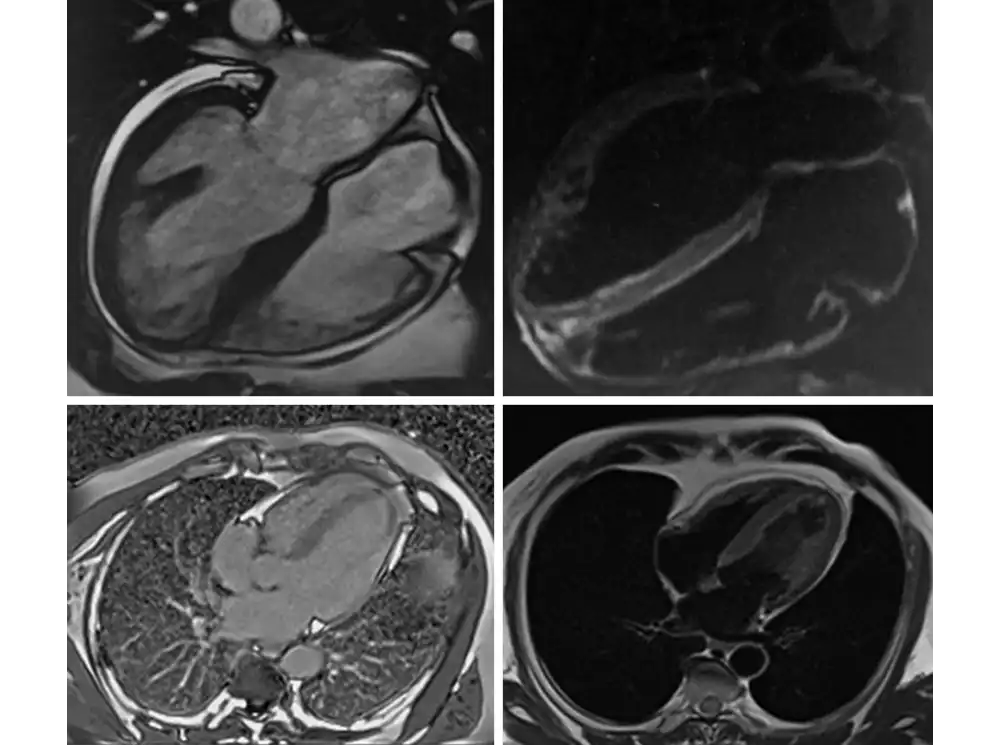

Что видит врач на МРТ сердца

Во время МРТ специалист не наблюдает орган в реальном времени, как при УЗИ. Аппарат собирает сигналы от атомов водорода в тканях, а врач следит за качеством данных и параметрами съёмки. Затем компьютер преобразует сигналы в послойные изображения — срезы в разных проекциях (короткая, длинная ось, четырёхкамерная проекция). Это статические снимки, на которых видна анатомия сердца.

Они могут выполняться в следующих режимах:

нативные T1/T2-карты без введения контраста — показывают отёк, воспаление, инфильтрацию, избыток железа или диффузный фиброз миокарда;

фазово-контрастные последовательности — фиксируют направление и скорость кровотока, визуализируют турбулентность и регургитацию при клапанных пороках;

позднее контрастное усиление позволяет лучше видеть необратимые изменения после инфаркта или миокардита.

Чтобы исследовать орган в действии, используют так называемый кинорежим (киноМРТ) — многократную съёмку одного и того же участка, синхронизированную с ЭКГ. После обработки врач получает видеопетли. На них можно видеть, как двигаются стенки, открываются клапаны и полости заполняются жидкостью. Именно эти кадры позволяют оценить фракцию выброса, регургитации и сократимость сердечной мышцы.

T-взвешенные изображения — это разные режимы, позволяющие выделить анатомию тканей (T1) или патологические изменения (T2). К примеру, по T1-снимкам врач может оценить структуру миокарда, а по T2-изображениям — выявить отёки, воспаления, ишемические повреждения.